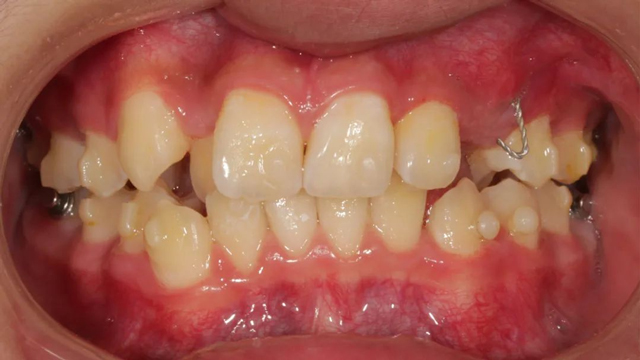

谈到具体的治疗方案,王亚楠医生表示,整体的治疗步骤是先拔除多生牙,一周后拆线,拆线当天拔除滞留乳牙,并对埋伏阻生尖牙行开窗术,通过粘贴牵引扣进行牵引,一周后开始佩戴隐形牙套。

据介绍,这个病例最复杂之处就是阻生牙的牵引。从矫正开始,医生以目标为向导制定矫正步骤,利用隐形牙套的优势,以及牙根可视化引导牙齿走向目标位,过程中密切关注阻生尖牙的方向及萌出情况,治疗过程中不断根据具体情况进行调整牵引方向和力的大小,牵引治疗几乎贯穿了矫正的全过程。

“由于这是一颗尖牙,外形比较圆润,并且是口内牙根最长的牙齿,矫治器力不太容易表达,所以移动时会更难一些,从牙齿出龈到建颌,每一步都离不开我们精心的设计。”